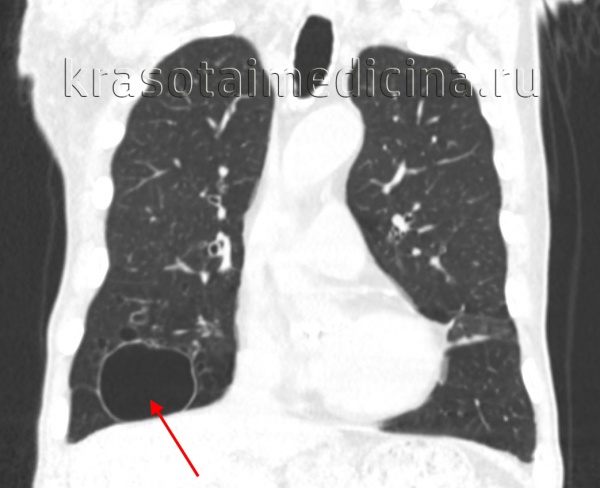

(Слева) На аксиальной КТ с КУ у пациента с лимфангиолейомиоматозом в легких визуализируются множественные кисты различного размера, разбросанные в неизмененной легочной ткани. Кисты диффузно распределены, имеют тонкую, но различимую стенку. Сопутствующих узелков в легких не выявлено.

(Справа) На аксиальной КТ без КУ у курильщика с лангергансоклеточным гистиоцитозом визуализируются мелкие узелки и кисты в верхних долях. Некоторые из них имеют толстые узловатые стенки и неправильную форму. (Слева) На аксиальной КТ с КУ у пациента с лимфоидной интерстициальной пневмонией в левом легком визуализируются разбросанные тонкостенные кисты. Лимфоидная интерстициальная пневмония чаще всего возникает на фоне иммунодефицита, преимущественно на фоне болезни Шегрена.

(Справа) На аксиальной КТВР у пациента с идиопатическим легочным фиброзом в базальных отделах с обеих сторон визуализируются множественные сгруппированные кисты в виде «сот» с -, объединенные в слои и имеющие общие стенки. Обратите внимание на сопутствующие тракционные бронхоэктазы, сопоставимые с фиброзом.